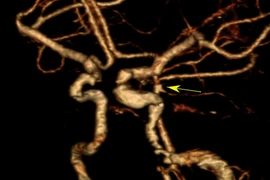

Người phụ nữ 47 tuổi sau khi tắm đột ngột đau đầu dữ dội kèm nôn ói vì xuất huyết dưới nhện do vỡ túi phình mạch máu não. May mắn, bệnh nhân được các bác sĩ cứu sống kịp thời.

Sau tắm hôn mê do vỡ túi phình mạch máu não

Vỡ túi phình mạch máu não gây xuất huyết dưới nhện còn có thể dẫn đến các hậu quả nặng nề như nhồi máu não, giãn não thất.... Người dân khi đau đầu, đặc biệt đau đầu cổ đột ngột, dữ dội cần cẩn thận.